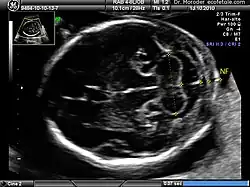

Procedure

Nuchal scan (NT procedure) is performed between 11 and 14 weeks of gestation, because the accuracy is best in this period. The scan is obtained with the fetus in sagittal section and a neutral position of the fetal head (neither hyperflexed nor extended, either of which can influence the nuchal translucency thickness). The fetal image is enlarged to fill 75% of the screen, and the maximum thickness is measured, from leading edge to leading edge. It is important to distinguish the nuchal lucency from the underlying amniotic membrane.[9]

Normal thickness depends on the crown-rump length (CRL) of the fetus. Among those fetuses whose nuchal translucency exceeds the normal values, there is a relatively high risk of significant abnormality.